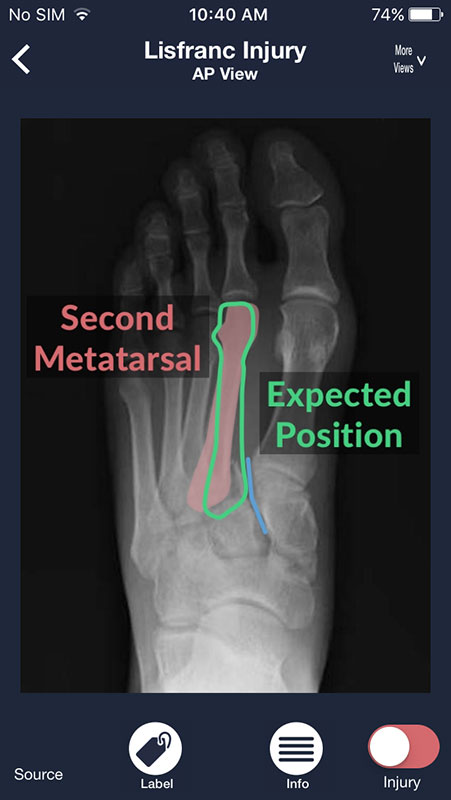

The app we reviewed today, called Sublux, is one of them. It is a quick reference for a plain radiography designed to help medical students, residents, and even seasoned physicians interpret the X-ray images of different body systems and common pathologies.

The Sublux app includes over 200 examples of different X-ray pathologies for nearly every area of the body with evidence-based treatments.

You can swipe the screen to navigate through the series of images. Each following image is annotated and contains a piece of advice on what to look for on a radiograph in order to distinguish between normal anatomy and abnormalities/pathologies.

There are two buttons below each image. First, Label button annotates the structures in the first image, showing them in different colors with names.

The other button, Injuries, features the list of most common injuries/pathologies related to a particular body part. For example, shoulder injuries such as AC joint disruption or proximal humerus fracture, or heart failure or pulmonary nodule in chest radiographs.

While in the Injury view, you can also select Label to view any abnormalities annotated, or Info button which provides users with the explanation of the presentation and X-ray findings, as well as management recommendations, without references used.

Tapping on Source shows the author of the image as well as the website the image was taken from (it is Radiopaedia.org in most cases).

Most radiographs can be viewed from multiple angles. Simply tap on More Views above each image and choose between different views.